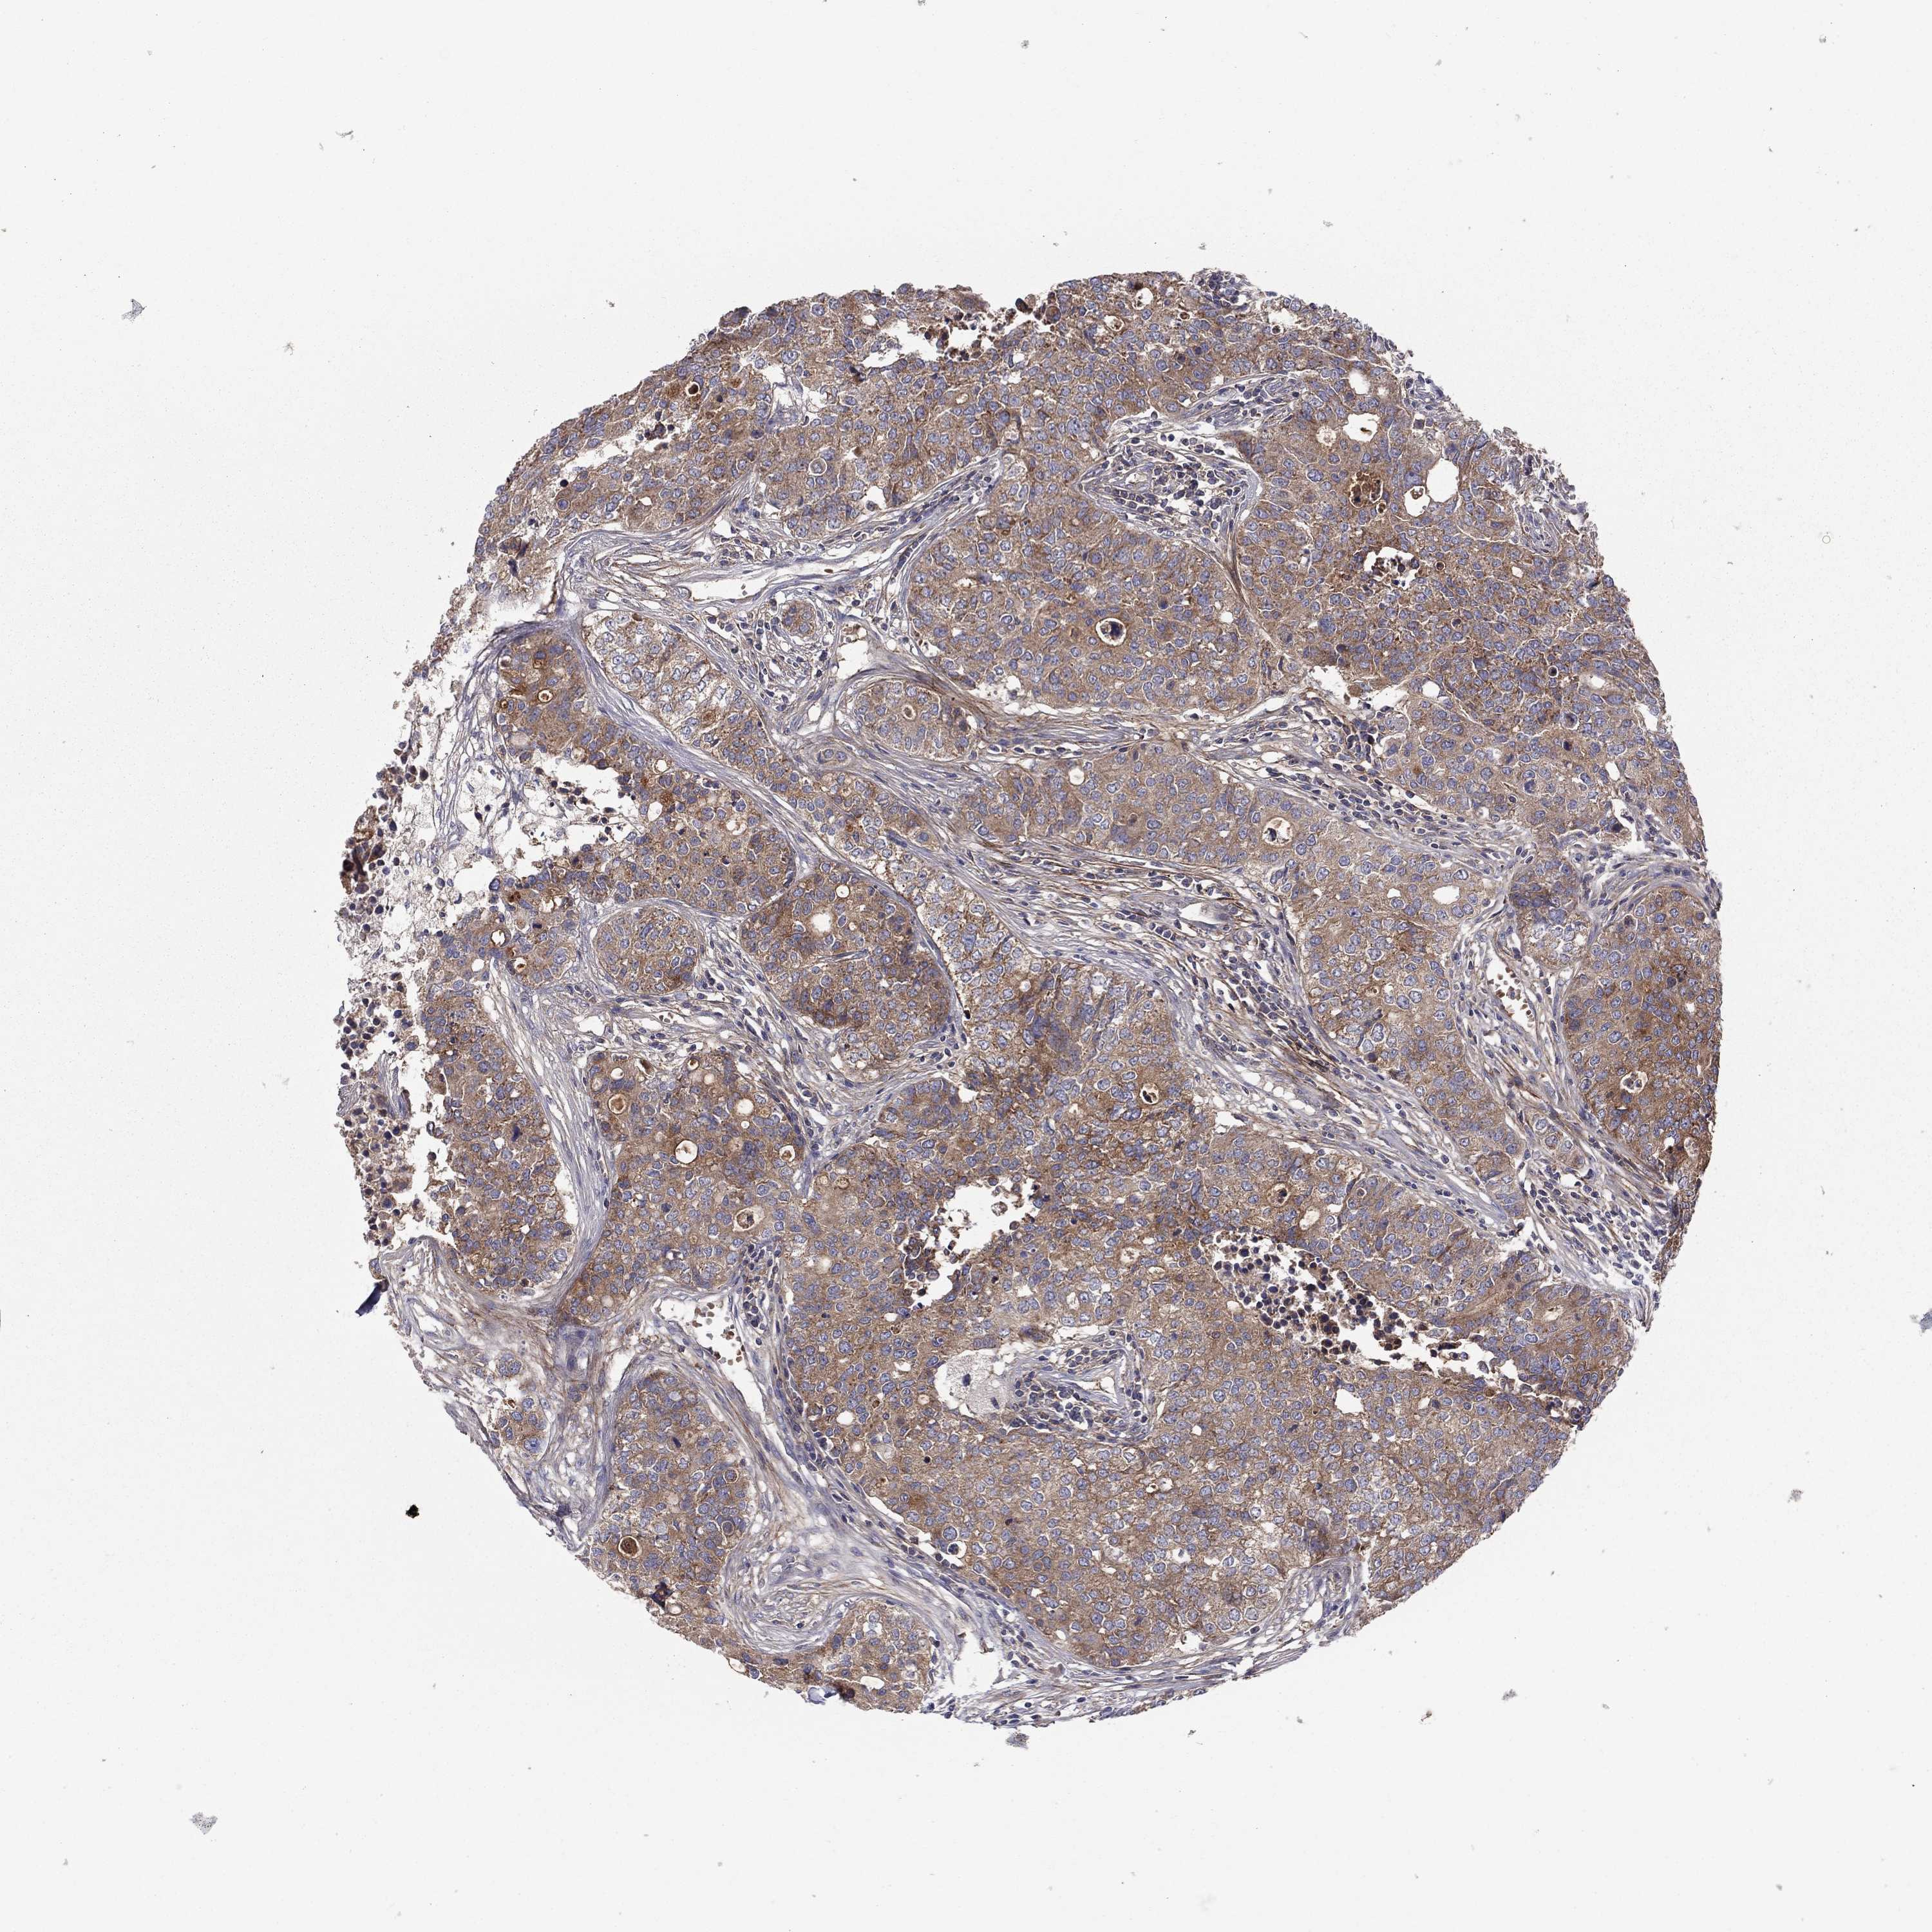

CARCINOID - Protein expressioni

A mouse-over function shows sample information and annotation data. Click on an image to view it in a full screen mode. Samples can be filtered based on level of antibody staining by selecting one or several of the following categories: high, medium, low and not detected. The assay and annotation is described here.

Antibody stainingi

Antibody staining in the annotated cell types in the current human tissue is reported as not detected, low, medium, or high, based on conventional immunohistochemistry profiling in selected tissues. This score is based on the combination of the staining intensity and fraction of stained cells.

Each image is clickable and will lead to virtual microscopy that enables deeper exploration of all samples and also displays staining intensity scores, fraction scores and subcellular localization as well as patient and tissue information for each sample.

Antibody HPA065983

Antibody HPA071879

Carcinoid, malignant, NOS